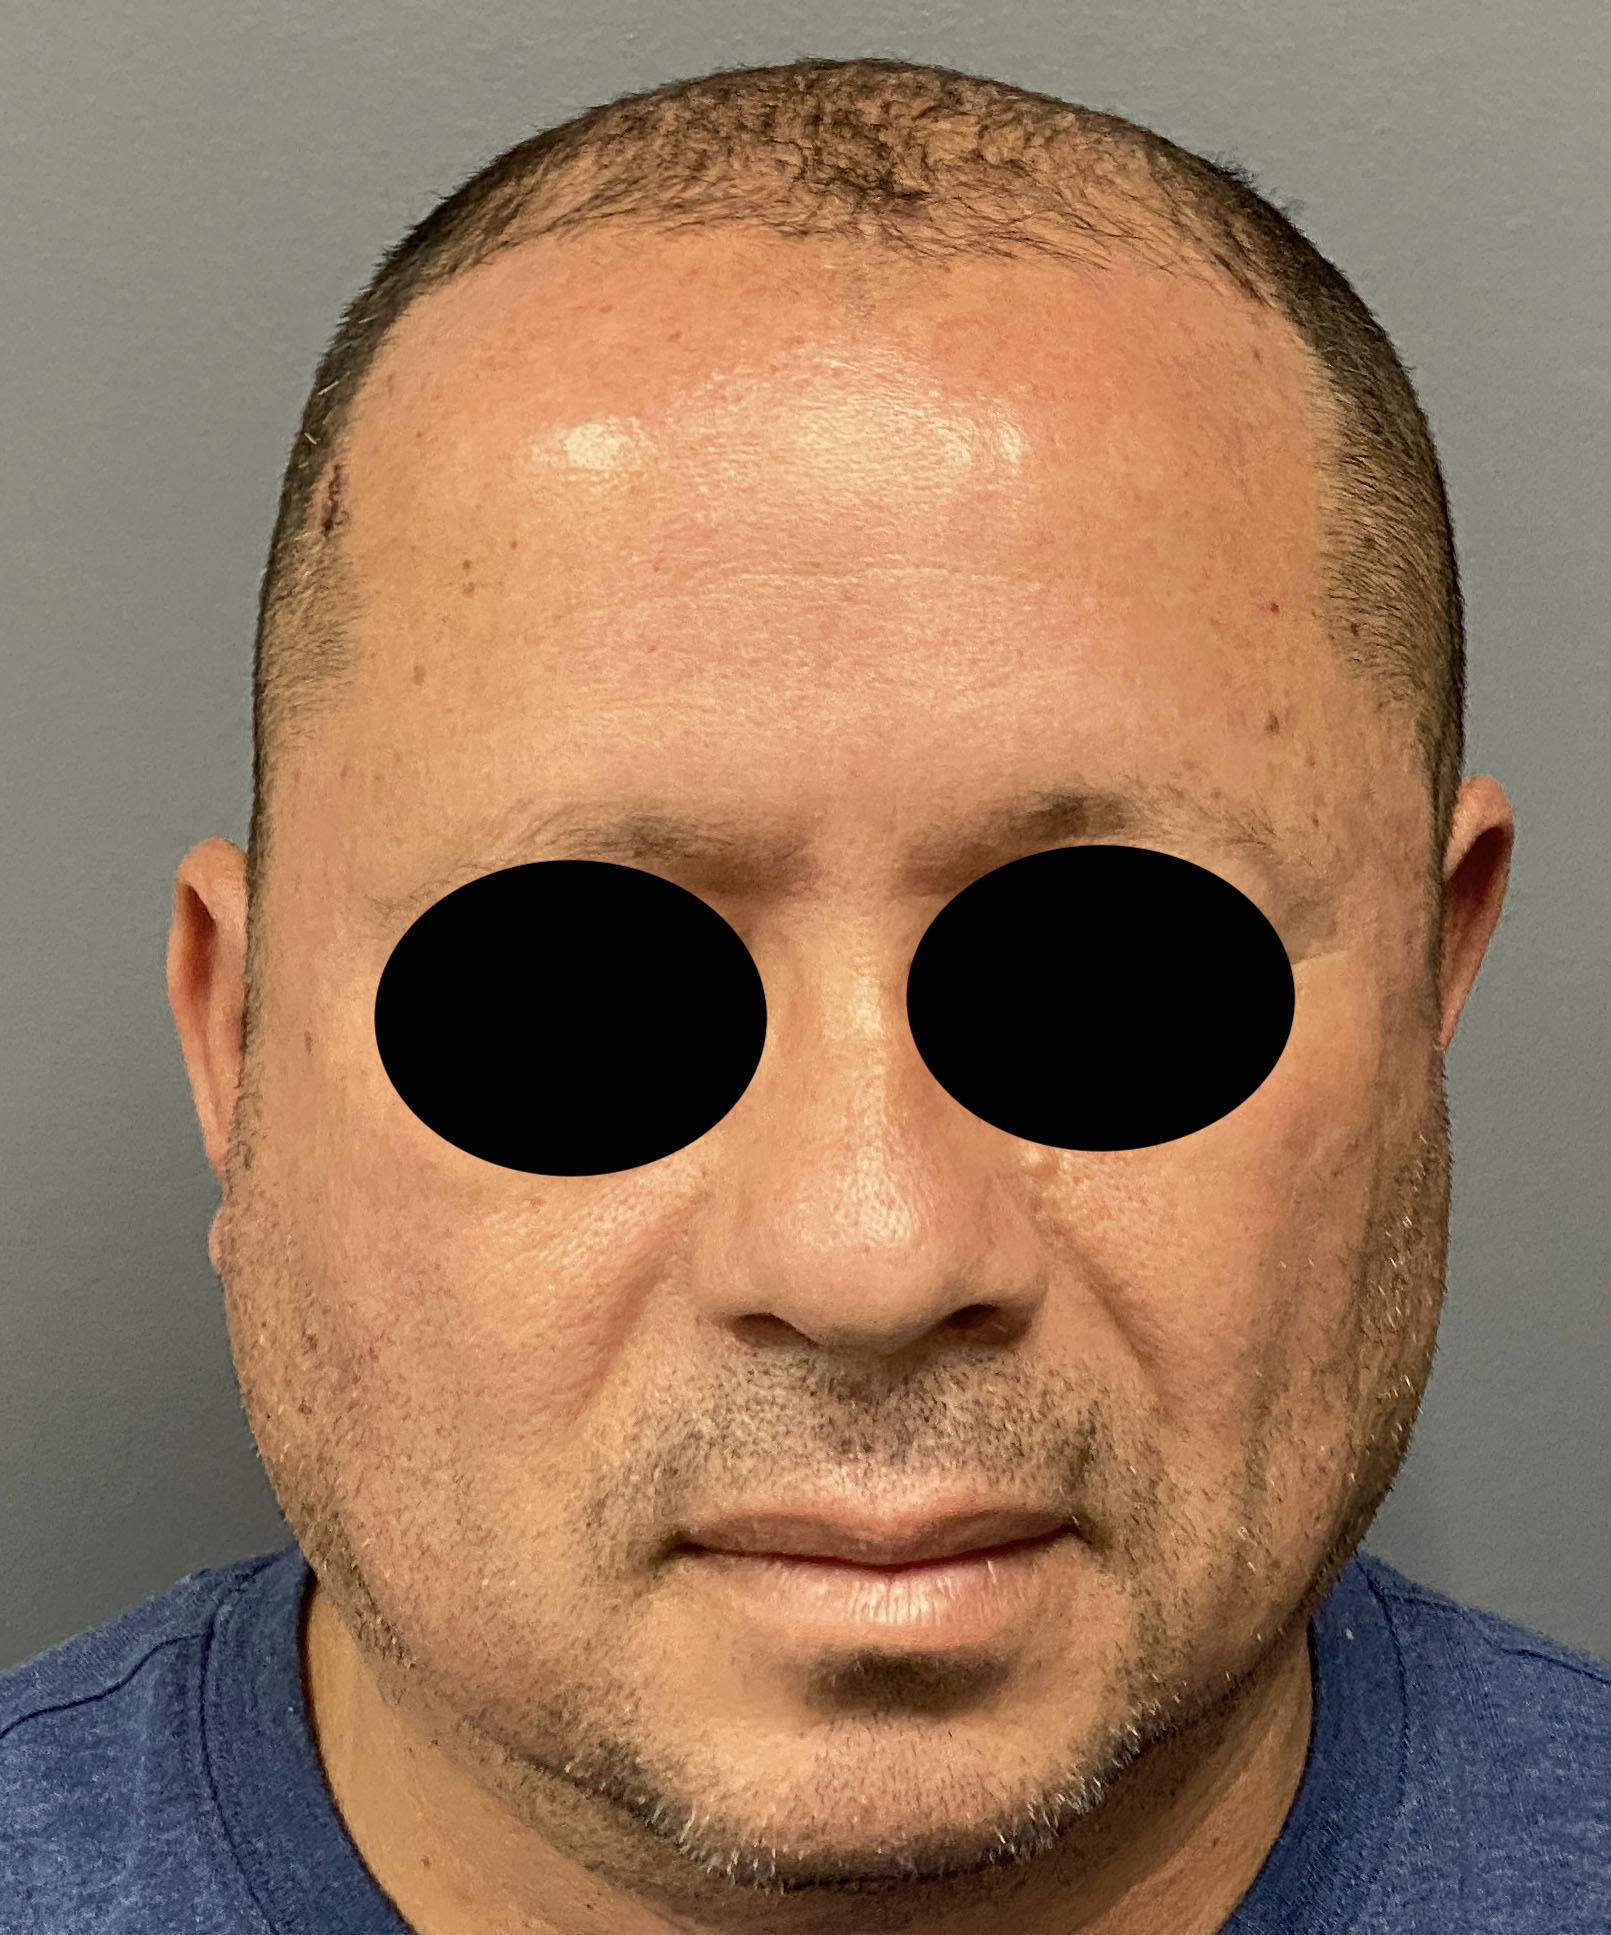

Patient 100

Desire for reshaping of an asymmetric flat back of the head in a shaved head male.

A combined back of the head reshaping procedure was done with a custom skull implant, sagittal ridge reduction and a right temporal muscle reduction.

Desire for reshaping of an asymmetric flat back of the head in a shaved head male.

A combined back of the head reshaping procedure was done with a custom skull implant, sagittal ridge reduction and a right temporal muscle reduction.